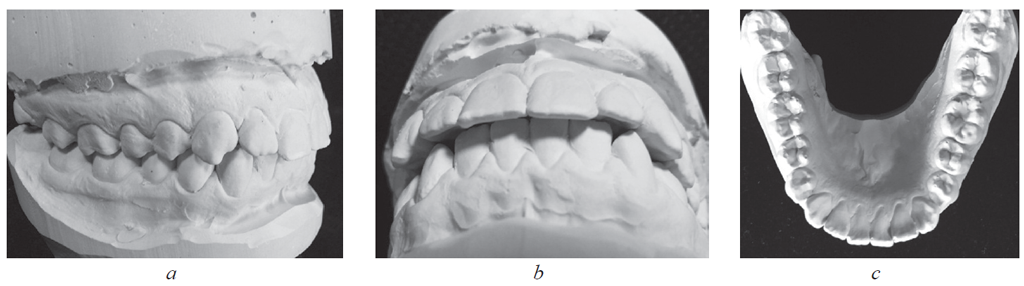

Материал и методы. Обследованы 62 человека первого периода зрелого возраста в двух клинических группах. В 1-ю группу вошли 24 пациента с физиологической окклюзией, а во 2-ю (38 человек) — с патологической окклюзией. В каждой группе были выделены пациенты с протрузией и ретрузией резцов. Вертикальное перекрытие оценивали на томограммах и гипсовых моделях челюстей между горизонтальными линиями, проходящими через режущие края резцов верхней и нижней челюстей параллельно окклюзионной плоскости.

Результаты. У пациентов 1-й группы с протрузией резцов межрезцовый угол составил 149,55 ± 3,92°, торк верхних резцов — 24,36 ± 2,39°. При ретрузии резцов величина межрезцового угла составила 151,47 ± 2,94°, торк верхних резцов — 5,85 ± 1,42°. При этом величина вертикального перекрытия соответствовала величине сагиттального перекрытия и не превышала 2–3 мм. У пациентов 2-й группы, как правило, отмечалось нарушение формы зубных дуг в переднем отделе.